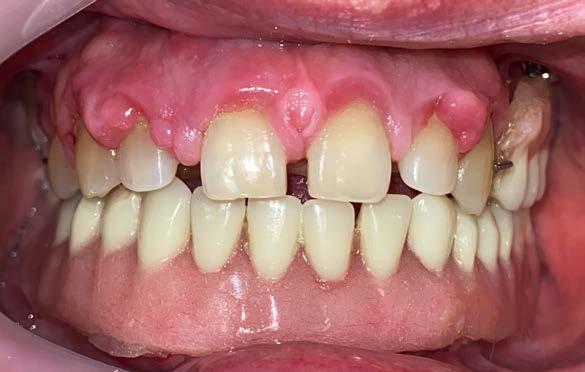

Figura 3. Fotografías intraorales.

hace 8 años por lo que toma 30 mg de nifedipino cada 12 horas, amlodipino 5 mg cada 24 horas, telmisartan 40 mg cada 12 horas y metropolol 100 mg cada 12 horas, además comenta padecer diabetes mellitus tipo II desde hace 7 años por lo que también toma 50 mg de metformina cada 12 horas y dapagliflozina 10 mg cada 24 horas. Clínicamente se observó una encía roja y sangrante, profundos sondeos, una notable hiperplasia gingival, depósitos de cálculo y movilidad dental grado III en todos los órganos dentarios a excepción del segundo premolar superior derecho al canino superior izquierdo, quienes presentaban una movilidad grado II. Radiográficamente se encontró una pérdida de inserción radiográfica avanzada generalizada

en la arcada inferior, y grupos molares de ambos cuadrantes superiores (Figura 1), los únicos órganos dentarios con posibilidad de preservación en boca a través de terapia periodontal se encontraron en el sector anterior de la arcada superior anteriormente mencionados con movilidad grado II

(Figura 2). Por lo que se diagnostica con periodontitis generalizada, estado IV, grado C (Figura 3).

Posteriormente se abordó la fase quirúrgica: se realizaron las extracciones de los órganos dentarios sin posibilidad de mantenerse en función en boca, se efectuó el legrado alveolar para retirar tejido infectado, además de realizar la exéresis del tejido hiperplásico, y regularización ósea para posteriormente producir la sinéresis de los tejidos a través de una sutura continua simple con sutura absorbible Vicryl 3-0 (Figura 7).

Concluida la intervención quirúrgica se efectuó la inserción de las prótesis inmediatas previamente fabricadas colocando acondicionador de tejidos Softy Autocurable NicTone al interior

Figura 9. A) Fotografías intraorales a la semana de la intervención quirúrgica. B) Fotografías intraorales a las 2 semanas de la intervención quirúrgica.

de ambas prótesis y adaptándolas a los rebordes alveolares residuales (Figura 8).

Finalmente se realizaron citas de control para retirar las suturas y supervisar la correcta cicatrización de los tejidos y readaptación de las prótesis inmediatas a la primera y segunda semana posteriores a la intervención quirúrgica (Figura 9). Se introdujo al paciente a un sistema de revisiones periódicas para evaluar las condiciones de los tejidos y eventualmente transicionar a una rehabilitación protésica definitiva.